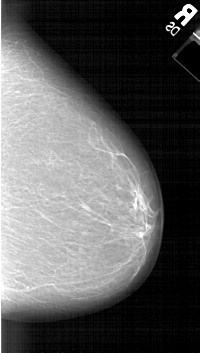

A_1308_1.LEFT_CC

LEFT_CC LINES 6286 PIXELS_PER_LINE 3556 BITS_PER_PIXEL 12 RESOLUTION 43.5 OVERLAY